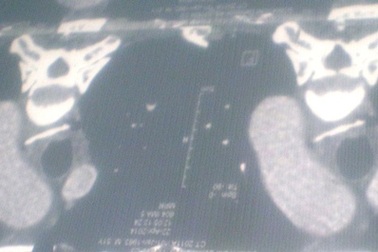

Xương gà xuyên thủng thực quản, bệnh nhân suýt tử vongNhập viện trong tình trạng sốt cao, đau tức ngực, ho khạc ra máu,… qua chẩn đoán hình ảnh, bác sĩ ghi nhận bệnh nhân bị hóc xương gà gây thủng thực quản. Không thể gắp xương bằng nội soi, bác sĩ buộc phải mổ cấp cứu lấy mảnh xương dài 3cm cứu bệnh nhân.

Suýt tử vong vì xương gà đâm thủng thực quản, phế quảnNhập viện trong tình trạng sốt cao, đau ngực, khó thở… qua chẩn đoán hình ảnh, bác sĩ ghi nhận bệnh nhân bị hóc xương gà gây thủng thực quản, phế quản. Không thể gắp xương bằng nội soi, bác sĩ buộc phải mổ cấp cứu lấy mảnh xương dài 3cm cứu bệnh nhân.